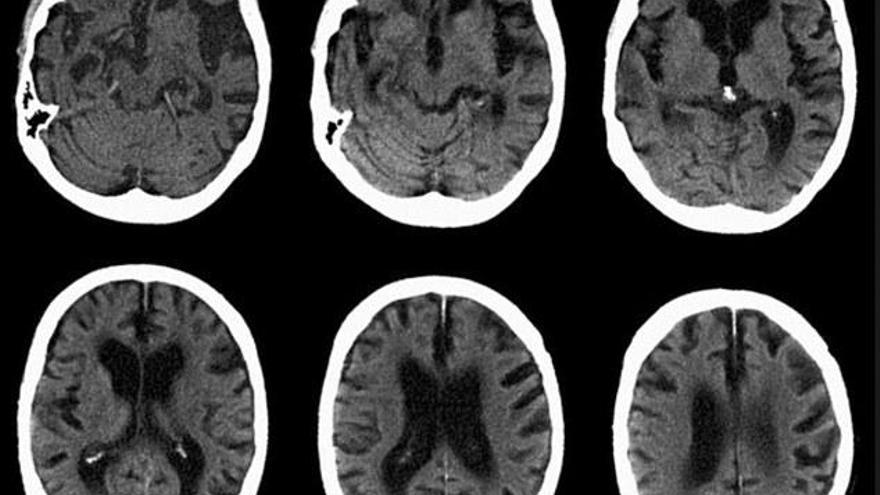

Els investigadors van injectar el virus amb el gen en dues àrees del cervell dels ratolins on podria desenvolupar l'Alzheimer, en l'hipocamp (que controla la memòria a curt termini) i el còrtex (que controla la memòria a llarg termini), i que són les primeres on comencen les plaques amiloides.

Els animals van ser tractats en els primers episodis de la malaltia, quan encara no compten amb aquestes plaques, i quatre mesos després es va constatar que els ratolins que havien rebut el gen tenien molt poques d'aquestes plaques comparades amb el grup dels ratolins que no havien estat tractats.

Així mateix, no es va registrar pèrdua de cèl·lules cerebrals en l'hipocamp.